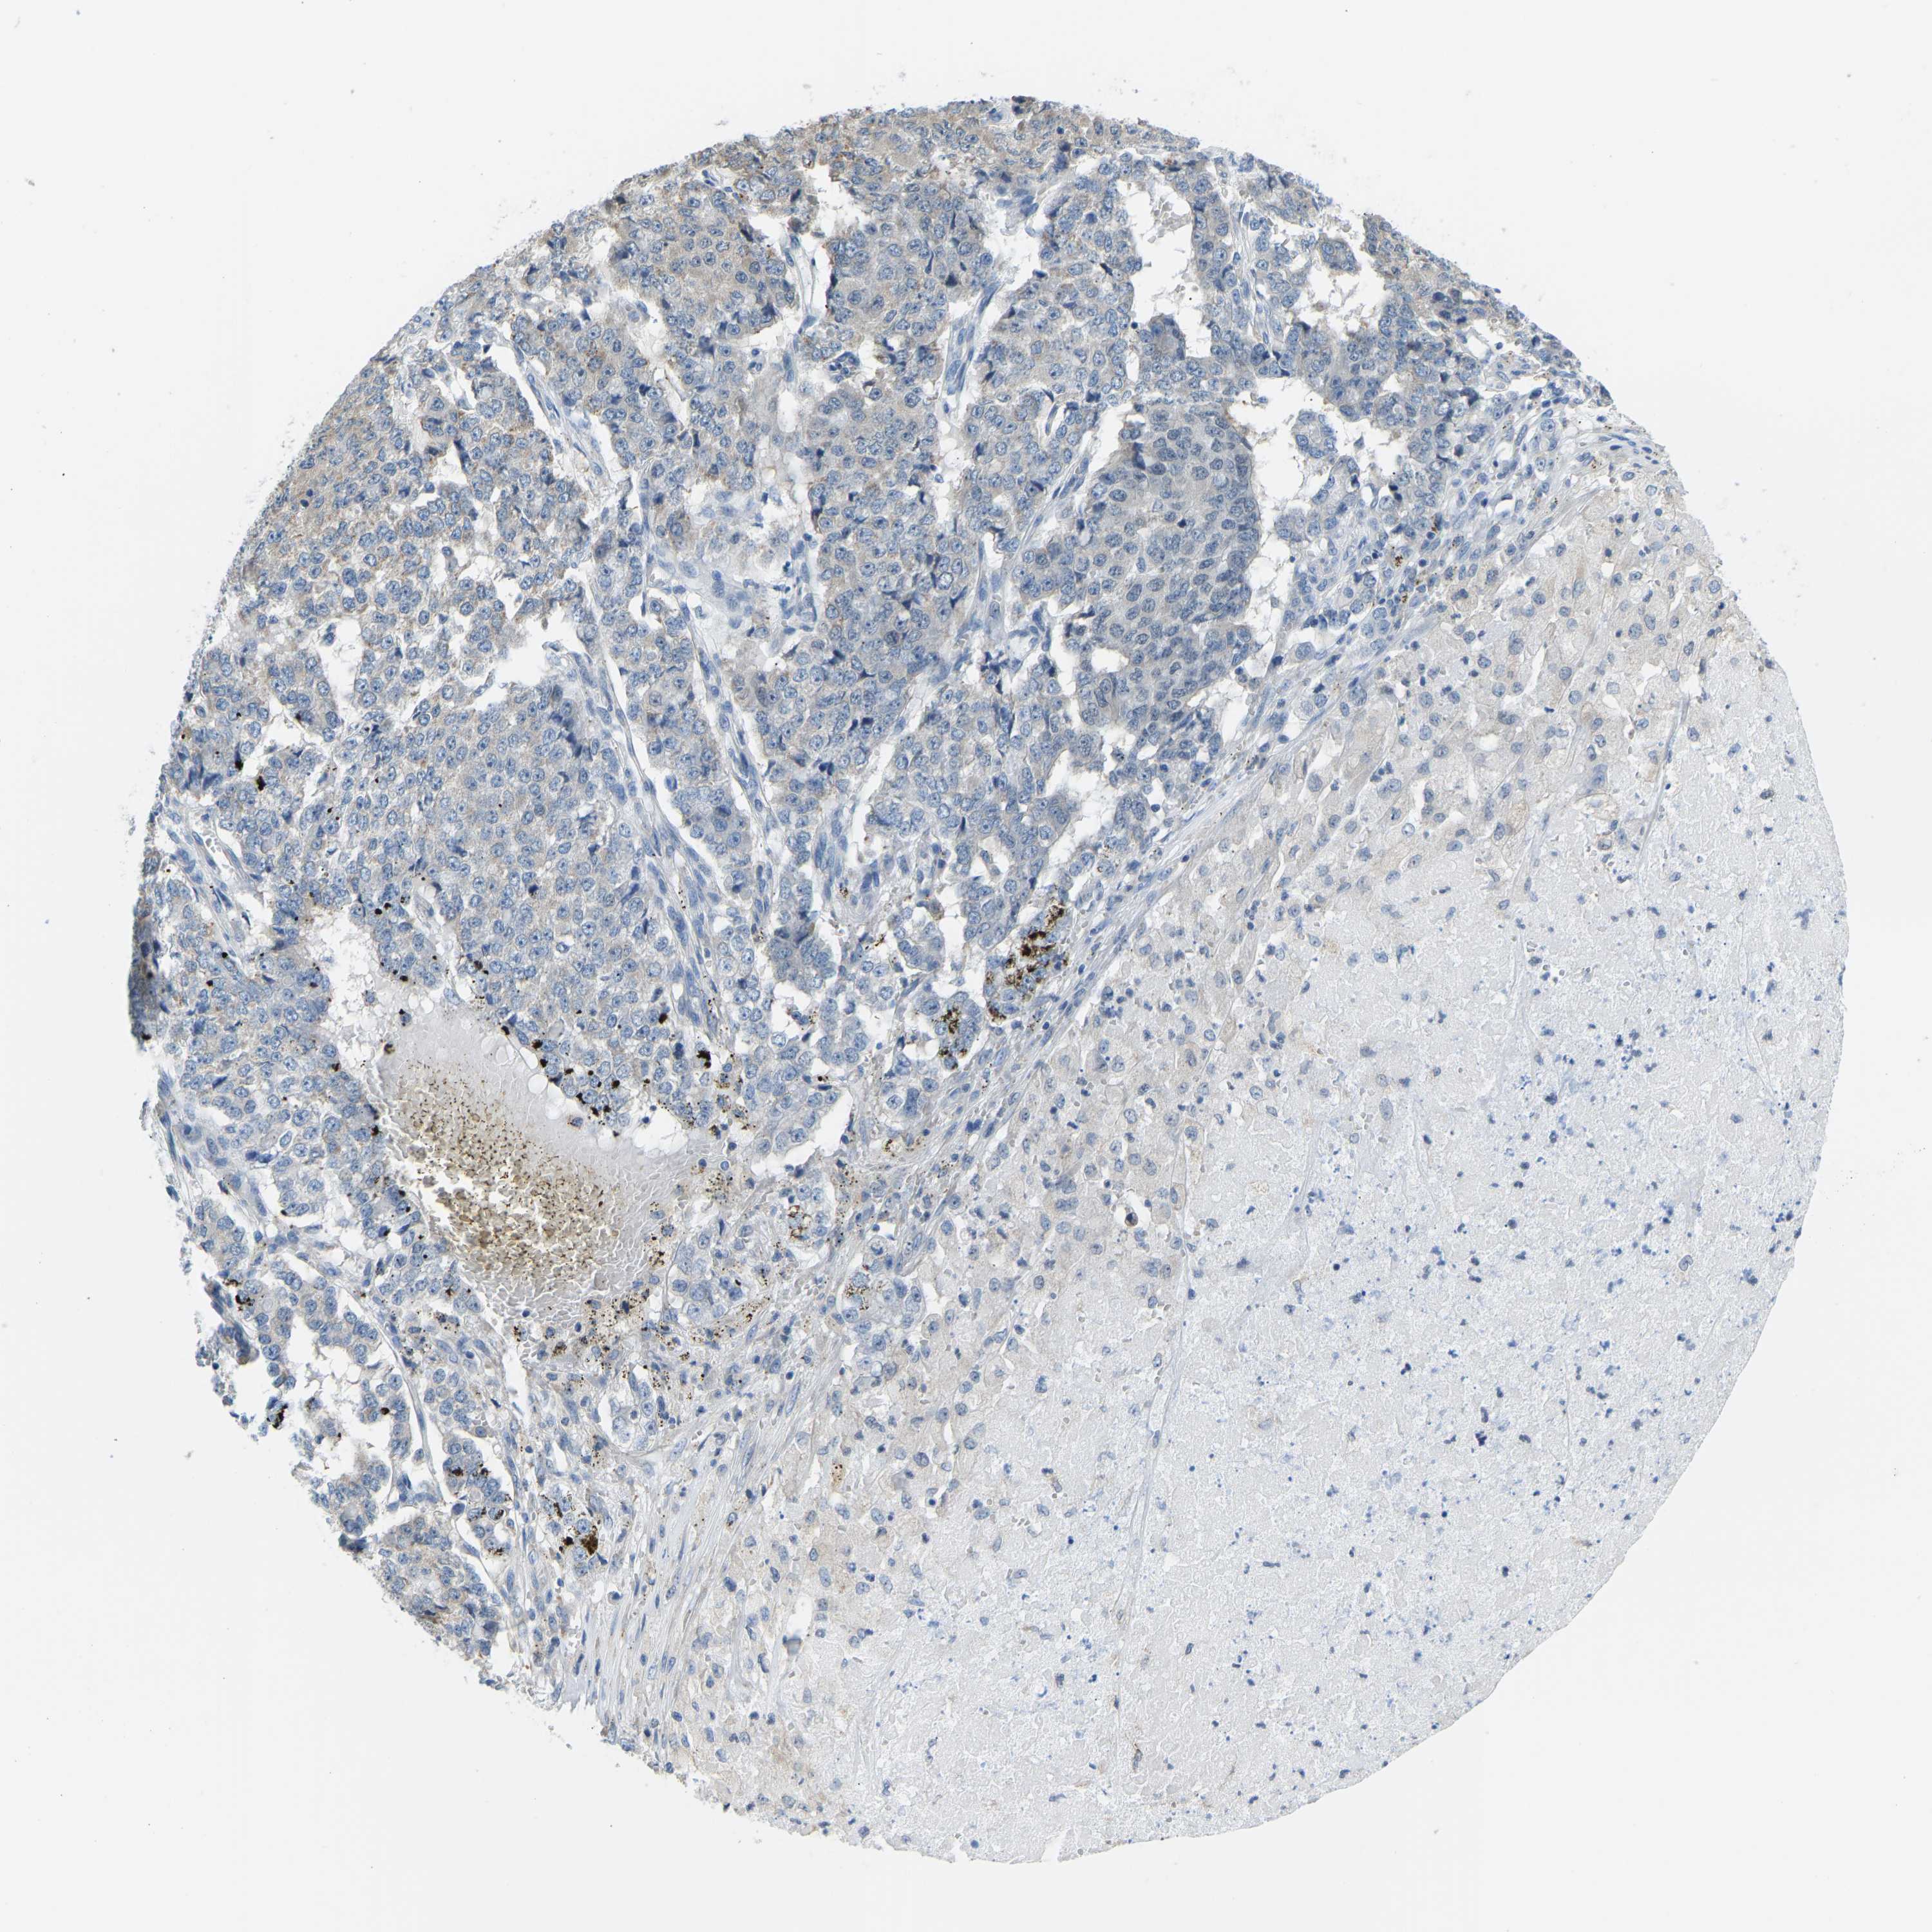

PANCREATIC CANCER - Protein expressioni

A mouse-over function shows sample information and annotation data. Click on an image to view it in a full screen mode. Samples can be filtered based on level of antibody staining by selecting one or several of the following categories: high, medium, low and not detected. The assay and annotation is described here.

Note that samples used for immunohistochemistry by the Human Protein Atlas do not correspond to samples in the TCGA dataset.

Antibody stainingi

Antibody staining in the annotated cell types in the current human tissue is reported as not detected, low, medium, or high, based on conventional immunohistochemistry profiling in selected tissues. This score is based on the combination of the staining intensity and fraction of stained cells.

Each image is clickable and will lead to virtual microscopy that enables deeper exploration of all samples and also displays staining intensity scores, fraction scores and subcellular localization as well as patient and tissue information for each sample.

Antibody HPA000660

Antibody HPA017929

Staining

High

Medium

Low

Not detected

Intensity

Strong

Moderate

Weak

Negative

Quantity

>75%

75%-25%

<25%

None

Location

Nuclear

Cytoplasmic/membranous

Cytoplasmic/membranous,nuclear

Adenocarcinoma, NOS